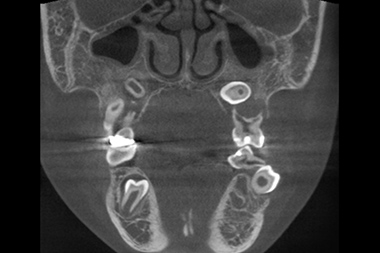

CT検査

3次元情報から、歯の位置・埋伏歯(歯冠の全てまたは一部が顎の骨や歯肉の中に埋まって出ていない歯)・過剰歯(決まった本数よりも多く歯が生えてくること)などを確認します。埋伏歯や過剰歯があると、歯が移動する際に適切な動きができなくなってしまうため、事前に不要な歯を確認しておく必要があります。また歯の移動に大きく関係する骨の厚さや距離などの情報も得られ、精度の高い矯正治療のための重要な情報源を採取することができます。

埋伏歯の位置や方向が確認できる

CT検査の例

CT検査で確認できる軸位断図

CTを使用すると、左記の軸位断図のように様々な角度の断面から歯の位置などの確認をすることができます。